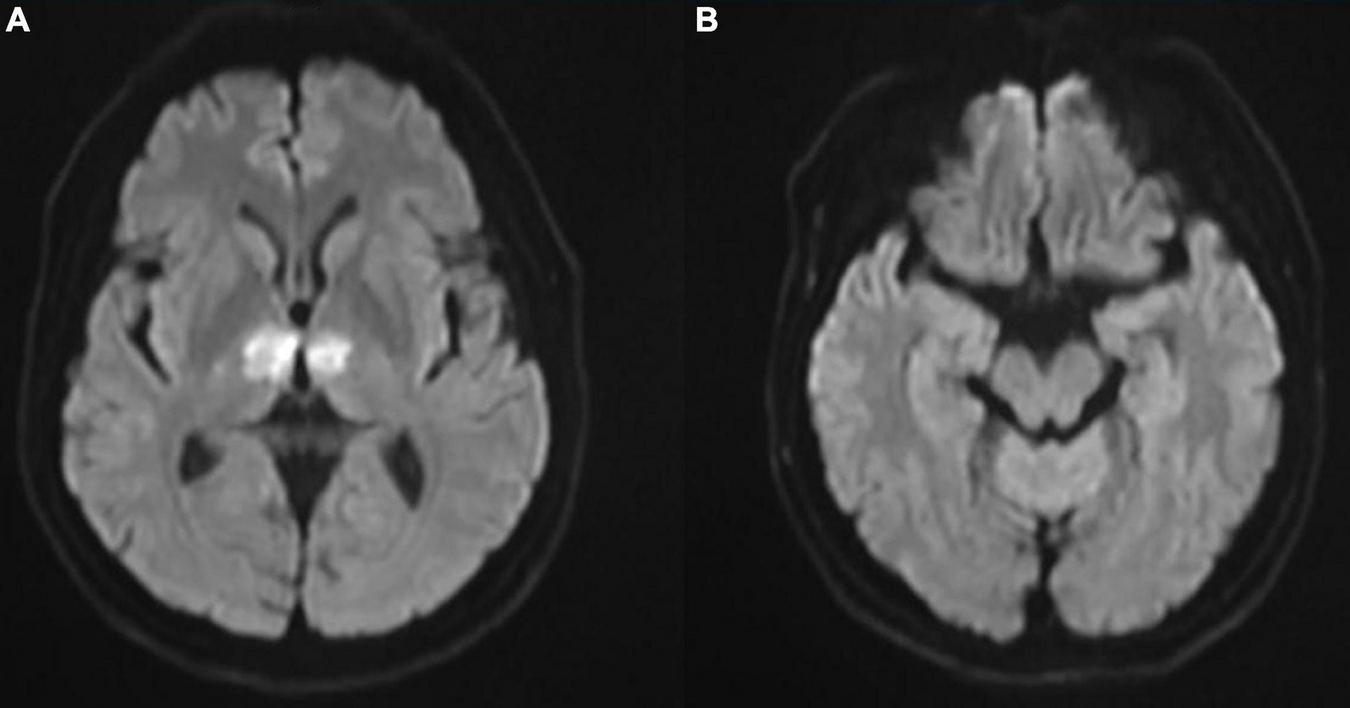

In the cardiac care unit, the patient’s consciousness gradually improved but still presented moderate drowsiness. To ascertain the pathogenesis of altered consciousness, a head MRI was ordered on the third day after the procedure. It showed symmetrical lesions in the paramedian thalamus, in the territory of the artery of Percheron. The lesions presented with an abnormal restriction of water diffusion on diffusion-weighted imaging (DWI) and hyperintensity in FLAIR and T2-weighted sequence on the paramedian thalamus level, without the midbrain involved (Figures 2, 3). MRI and corresponding clinic manifestations confirmed the diagnosis of an AOP infarction.

FIGURE 2

(A) Axial diffusion-weighted magnetic resonance imaging (MRI) showing bilateral paramedian thalamic hyperintense signal due to restricted diffusion and (B) no involvement on the midbrain level.